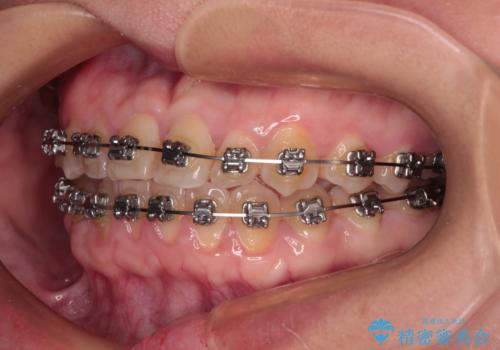

- 矯正装置

- メタルブラケット

- 前歯の反対咬合を気にして来院された患者様です。

当院にて同様の咬み合わせを治療した方からのご紹介ということもあり、ご紹介者と同じワイヤー矯正で早めに治療を終えることを希望されました。

骨格的に下顎が前方に位置していましたが、歯列矯正で改善できると判断し、ワイヤー装置にて矯正治療を行うこととしました。

このような咬み合わせの方の多くは、舌の突出癖が強い傾向にあり、反対咬合改善後に開咬となってしまい、なかなか治療が終わらないことがあります。

こちらの患者様は、舌のトレーニングを治療開始前から徹底的に実践していただき、僅か8ヶ月という短期間で治療を終えることができました。